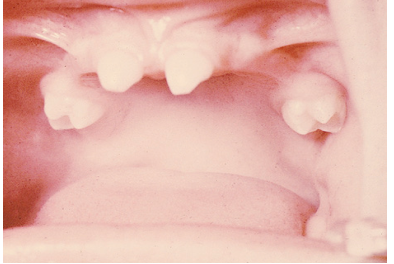

<p>What causes this developmental disturbance during the embryonic period?</p>

What causes this developmental disturbance during the embryonic period?

Ectodermal Dysplasia → abnormal development of one or more structures from the ectoderm leading to partial/complete anodontia (absence of some teeth or all teeth)

• Caused by: mutation in genes leading to abnormal ectodermal structure development.